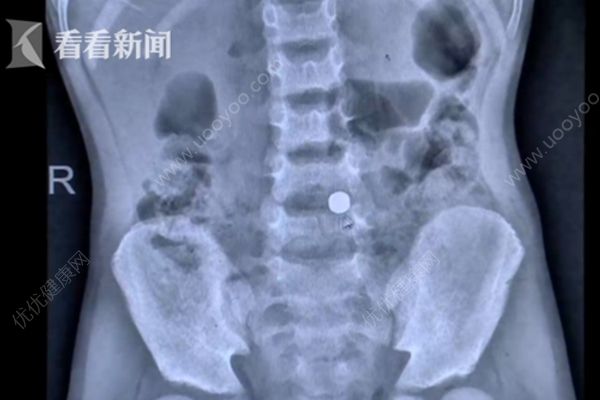

七岁男童浩浩出现了持续近一周的腹痛,父母带着浩浩来到医院就诊。医生通过腹腔镜找到了导致浩浩出现腹痛的“凶器”,原来是一根长达八厘米的棒棒糖棍子。

手术中,医生发现,浩浩体内的这根棍子距离腹腔大动脉仅仅一两厘米,如果不慎刺破大动脉,后果将不堪设想。无独有偶,8岁的小易前些日子也同样因为肚子疼到不行,来医院就诊。经过检查,医生在小易的腹腔内发现了一块纽扣大小的异物,经过手术取出后,医生发现,异物竟然是一块纽扣大小的磁铁。所幸,经过手术和后续的治疗,目前,两位孩子已经基本康复。